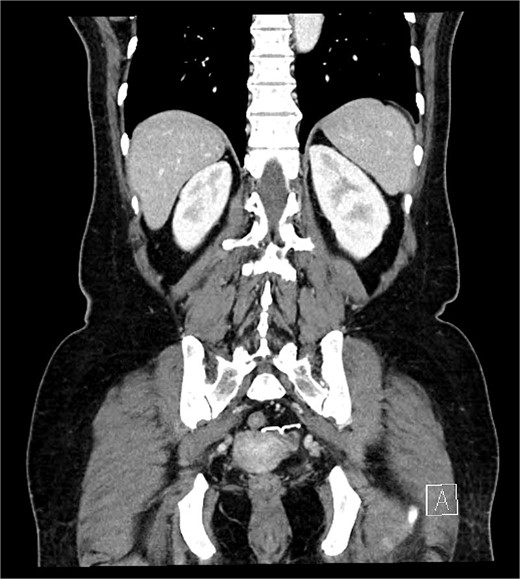

A 54-year-old woman, gravida 4, para 2, presented at the outpatient department with abnormal colonoscopy findings. She had a history of hypertension and underwent an IUD insertion for contraception one year after delivery in 2000. However, in 2007, when she visited the clinic for its removal, the IUD was not found on pelvic examination and ultrasound. The patient assumed that the IUD had been expelled spontaneously. Six months before her 2022 hospital visit, she experienced intermittent rectal bleeding and lower left abdominal pain, leading her to seek medical attention. Her medical history and physical examination, including a digital rectal examination, showed no notable abnormalities except for mild left lower quadrant tenderness. Routine laboratory investigations yielded unremarkable results. During colonoscopy, a foreign body was observed penetrating the sigmoid wall, surrounded by granulation tissue (Fig. 1). Subsequently, an abdominal simple X-ray and computed tomography scan were performed, revealing that the foreign body was an IUD, located next to the left side of uterus and entering the sigmoid colon (Figs 2 and 3).

IUD positioning adjacent to the left uterus and extending into the colon, observed on CT.